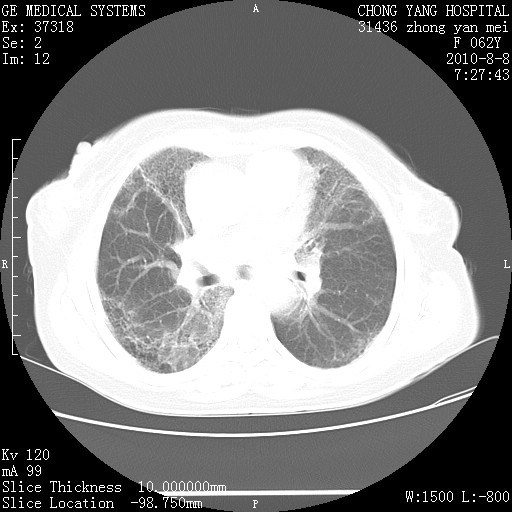

标题: CT28269:F62Y咳嗽胸痛数月。 [打印本页]

标题: CT28269:F62Y咳嗽胸痛数月。

两肺弥漫性间质纤维化伴继发性支扩。

考虑特发性肺间质纤维化

考虑两肺间质性肺炎并肺间质纤维化。

双肺间质纤维化合并感染、肺气肿

两肺间质纤维化并牵拉性细支气管扩张。

考虑两肺间质性肺炎并肺间质纤维化,肺气囊形成。

两肺间质改变,纵隔淋巴结肿大,需要考虑结节病的可能。